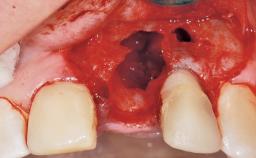

Immediate Flapless Placement of an Implant in a Maxillary Left Central Incisor Site

A 29-year-old female patient presented for treatment to replace the upper left central incisor tooth with an implant- supported restoration. The tooth had been intermittently symptomatic for the previous 12 months. The tooth had originally suffered trauma about 15 years previously. Several endodontic treatments had been performed, including an apicectomy procedure to retain the tooth. The patient was healthy and a non-smoker. She had reasonable expectations in regard to esthetic outcomes and the risk of marginal tissue recession following treatment. At medium smile, the gingival margins of the upper teeth were visible, with a display of 3 to 4 mm of the gingival margins. Gingival recession of tooth 21 and a discrepancy in the gingival levels between teeth 11 and 21 was observable during normal speech and smile.

| Soft Tissue Anatomy | Intact | Defective | |

| Socket Integrity | Damage to one or more bone walls |

| Bone Volume | Damage to one or more socket walls |

| Soft Tissue Contour and Volume | Slightly compromised |